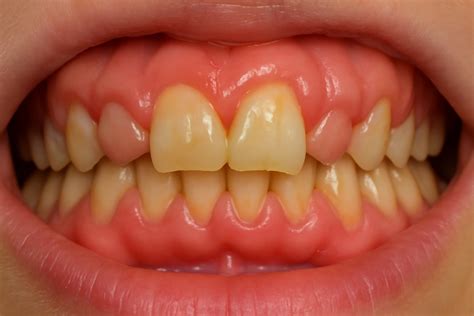

Ejemplo visual de hiperplasia gingival.

La apariencia típica incluye aumento de volumen gingival que inicialmente afecta papilas interdentales, pudiendo progresar hacia encía marginal y adherida. Aparece el dolor, cuyo tipo e intensidad puede variar, el enrojecimiento del tejido gingival, el sangrado, etc. La coloración puede oscilar desde rosa pálido en hiperplasias predominantemente fibrosas hasta rojo intenso en casos con componente inflamatorio significativo.